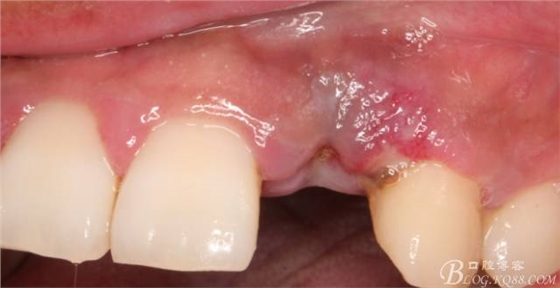

10天拆線一切正常,又過(guò)了兩周患者復(fù)診,自述期間無(wú)異常??趦?nèi)檢查,真的嚇了一跳,唇側(cè)鼓了個(gè)包,擠壓有白色分泌物溢出,絕對(duì)不是膿液,液體排除后,術(shù)區(qū)觸診空虛,外觀塌陷。這時(shí)候考研大夫的時(shí)刻到了,是先觀察一段時(shí)間再說(shuō)?還是馬上進(jìn)行處理?我的回答是:馬上處理!如果你沒(méi)有及時(shí)處理,而是放患者回家觀察,那么接下來(lái)會(huì)發(fā)生如下情況:1.回家后患者家屬及親友會(huì)有很多你可以想象得到的討論;2.患者及家屬會(huì)對(duì)你產(chǎn)生不信任,勢(shì)必會(huì)到其他門(mén)診或醫(yī)院檢查,他院大夫會(huì)不會(huì)發(fā)表對(duì)你不利的言論;3甚至?xí)蚁嚓P(guān)法律界人士找你討要說(shuō)法。